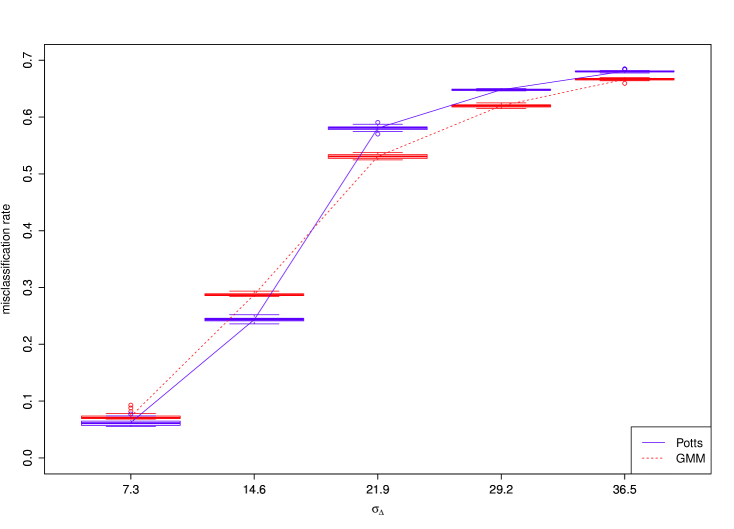

4.3 Sensitivity analysis

The amount of spatial variability in our application is quite small (standard deviation of ) relative to the size of the images (). We reran the model using external field priors with increasing levels of uncertainty ( up to , illustrated in Fig. 1) to measure the relationship between the strength of the prior and the resulting segmentation accuracy. The pixel-wise misclassification rates for the 27 cone-beam CT scans are shown in Fig. 4. We found that there was a strong relationship, with the proportion of misclassified pixels increasing sharply at first, but then gradually levelling off. As the uncertainty increases, we would expect that the misclassification rate would approach 86.8%, the accuracy that is observed without the external field prior.

We also measured the effect on segmentation accuracy when was fixed at zero, which is equivalent to an independent mixture of Gaussians. When the average misclassification rate was 7.3% (mean pairwise difference of 1.07% with standard deviation of 0.03). This indicates that the Potts model contributed very little to the result. Most of the spatial dependence in the model was accounted for by the external field prior, while the local smoothing of the labels made a small but significant difference. When was doubled to , the segmentation accuracy decreased overall but the contribution from the Potts model was larger (mean pairwise difference of 4.41% with standard deviation of 0.21). When the uncertainty was increased still further, the Potts model actually made the accuracy worse. This can be seen in Fig. 4 for . This is because the Potts model relies on the labels of the neighbouring pixels. If many of the pixels are misclassified, this will then bias the probabilities of the labels towards an incorrect value.